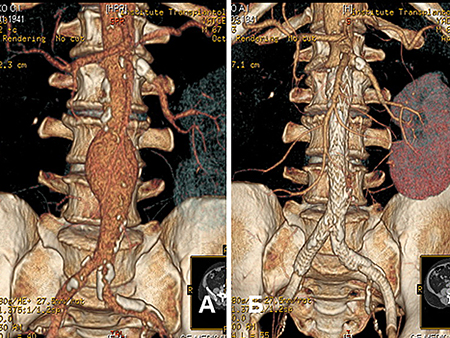

аневризма аорти

Рисунок 5. Аневризма черевної аорти:

А - до втручання, Б - встановлено стент-графт

Сенс втручання в ізолюванні мішка аневризми від кровотоку спеціальним пристроєм - стент-графтом. При цьому кровотік залишається всередині стент-графта, а порожнину аневризми, що знаходиться між зовнішньою поверхнею стент-графта і зміненою стінкою аорти, виключають із кровотоку. Це призводить до тромбозу порожнини аневризми (кров, що перебуває без руху, самостійно тромбується через короткий проміжок часу) з подальшим заміщенням сполучною тканиною.

Стент-графт - поєднання судинного ендопротеза зі стентом, являє собою трубку з ПТФЕ (політетрафторетилен), яку утримує в розкритому стані складний дротяний каркас, що нагадує пружний стент великого діаметра. Як і судинний протез, стент-графт може бути лінійним або біфуркаційним (конструкція, що за формою нагадує штани). У складеному стані стент-графт уміщається в трубку відносно невеликого діаметра, а в розкритому стані - повинен максимально відповідати незміненим ділянкам артерій, до яких прилягає. Підбір або виготовлення стент-графта здійснюється суто індивідуально згідно з даними комп'ютерної томографії або інших досліджень, що дають змогу індивідуально змоделювати ділянку аорти, що підлягає втручанню.

Хід операції: ендоваскулярний хірург через невеликий розріз стегнової артерії (частіше правої) вводить в аорту систему доставки - трубку зі стент-графтом у складеному стані. Під рентгенконтролем стент-графт максимально точно підводять до ділянки аневризми і розкривають таким чином, щоб обидва кінці графта щільно прилягали до незмінених ділянок аорти, забезпечуючи повну герметизацію мішка аневризми. Систему доставки видаляють, розріз артерії та шкіру зашивають.

За необхідності ізолювати не тільки аорту, а й змінені клубові артерії (а така необхідність виникає за більшості аневризм черевної аорти), використовують біфуркаційний стент-графт. Методика його встановлення дещо складніша і потребує хірургічного мінідоступу як до лівої, так і до правої стегнових артерій.